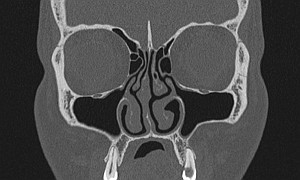

Околоносовые пазухи